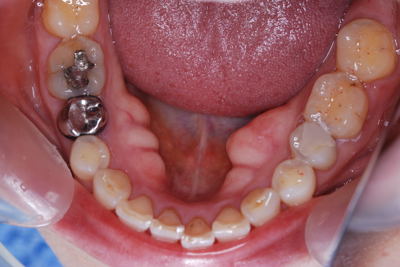

| これは、過剰歯です。おまけの様な小さい歯が余分にできる事があります。不思議ですね。 隣の歯にくっついている事もあり、別になっている事もあります。 |

![]() |

|